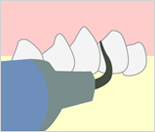

2.歯垢・歯石・着色除去

染出しの結果を基に、汚れの付いている着色部分を徹底的にきれいにしてきます。

歯垢(プラーク)・歯石除去

歯石(歯垢が固まったもの)の付着が見られた場合はスケーラーという超音波の器具を使って細部まで取り除きます。

歯石(歯垢が固まったもの)の付着が見られた場合はスケーラーという超音波の器具を使って細部まで取り除きます。